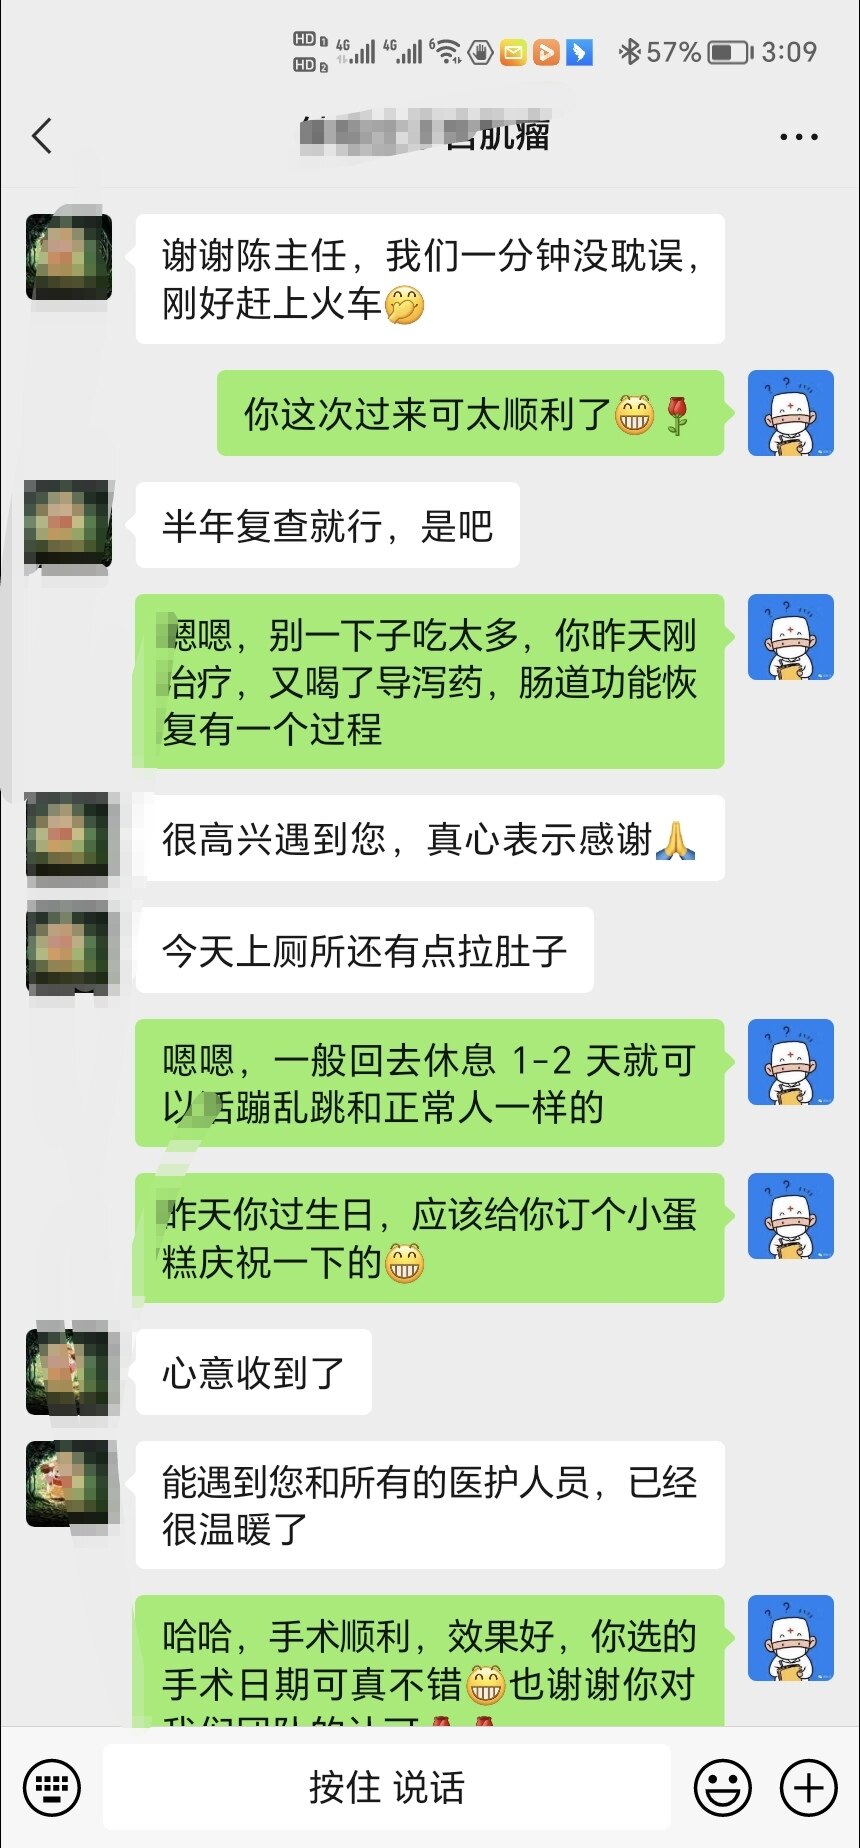

患者不愿意选择传统手术,在了解到海扶刀可以无创的治疗子宫肌瘤后,专门从天津至我们中心进行治疗,不到40分钟肌瘤就完全消融,患者今天复查显示肌瘤消融满意,病人今天下午就正常回家了。

并且很巧合的是,手术当天正好是患者的生日,也算是自己给自己一个特殊的礼物和一次难忘的经历。